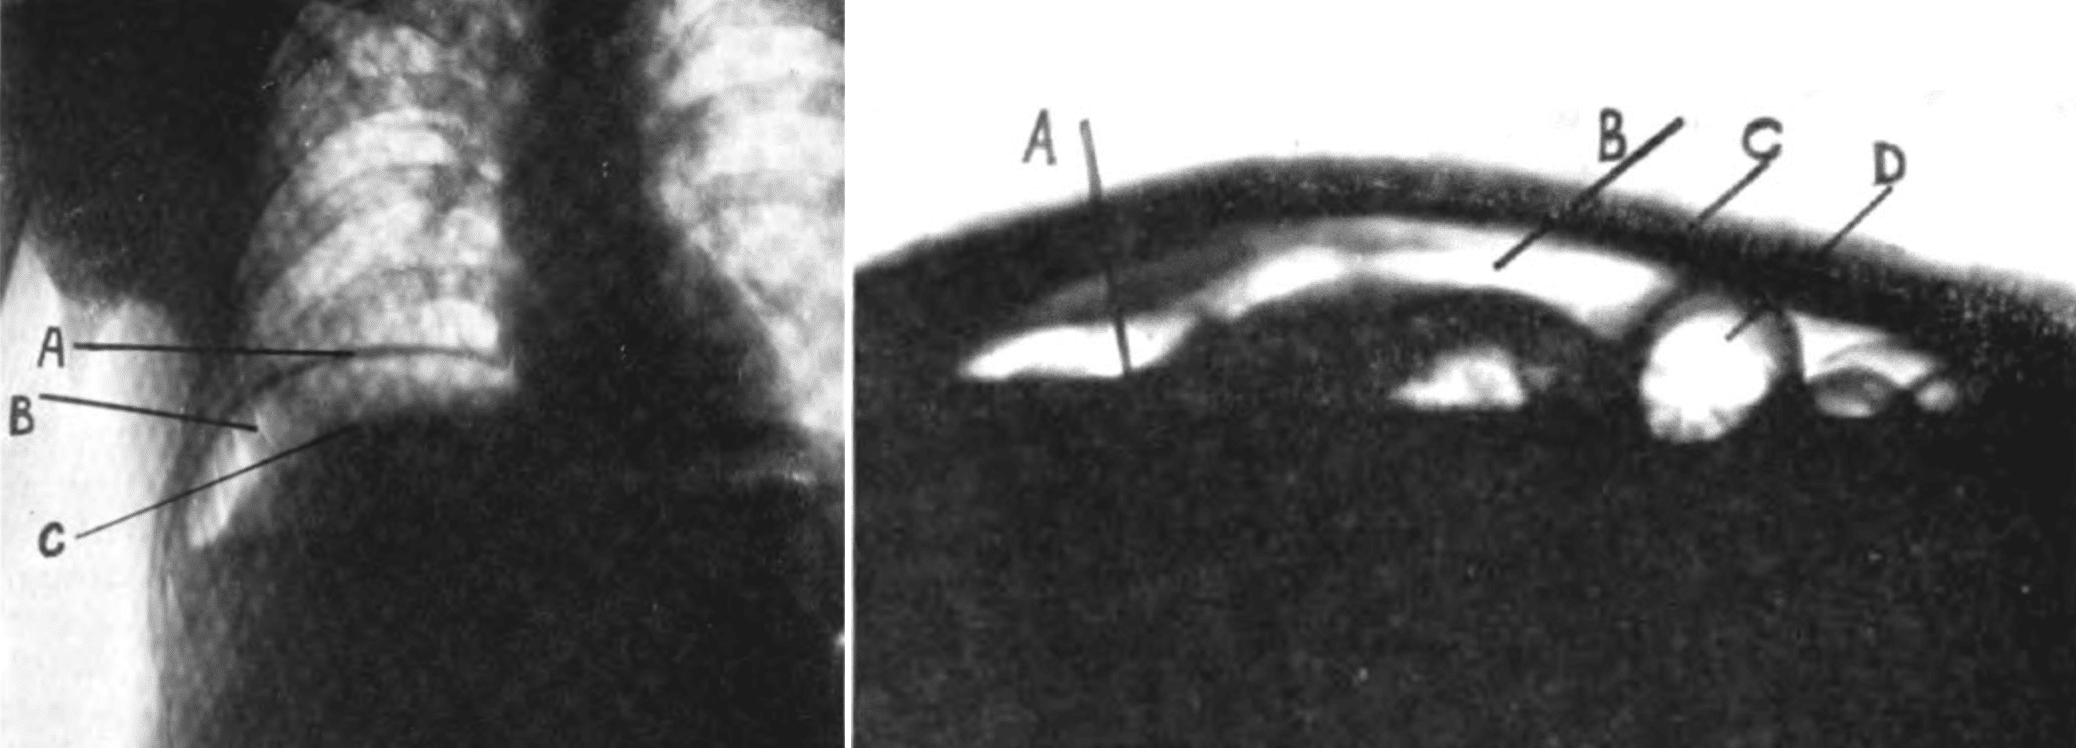

Left Fig.1. Erect X-ray A, dome of right diaphragm; B, free air under diaphragm; C, upper surface of liver.

Right Fig. 2. Supine decubitus X-ray A, level of fluid in free abdominal cavity; B, free air in abdominal cavity above the fluid level; C, anterior abdominal wall; D, loop of bowel containing air. Vaughn 1924